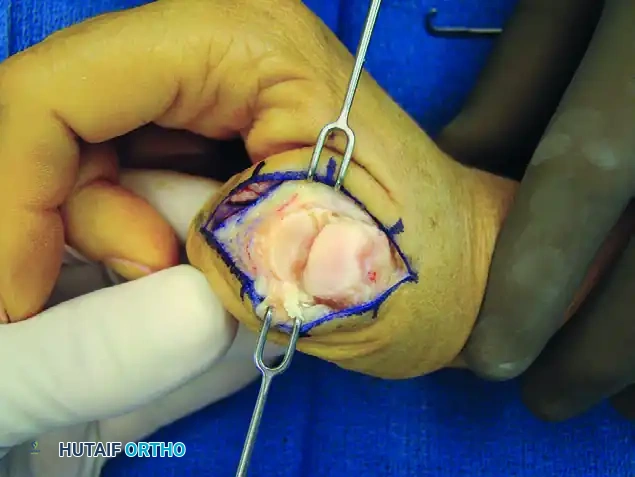

FIGURE 73-40A: Curved dorsal incision to allow safe dissection of sensory nerves from the underlying extensor apparatus.

2. Extensor Apparatus and Capsular Exposure

Once the superficial nerves are protected, the extensor apparatus is addressed to gain access to the joint capsule.

- Identify the extensor pollicis brevis (EPB) tendon and the radial aponeurotic fibers.

- Make a longitudinal incision through the EPB tendon and the radial sagittal band fibers. This interval allows for excellent exposure of the underlying dorsal capsule without compromising the centralizing forces of the extensor pollicis longus (EPL).

FIGURE 73-40B: Incision through the extensor pollicis brevis tendon and radial aponeurotic fibers exposing the dorsal capsule.